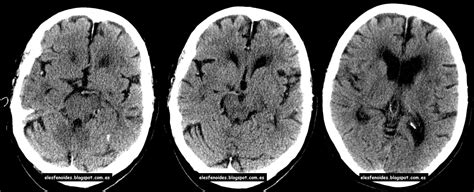

Isquemia cerebral é uma condição que ocorre quando não há fluxo sanguíneo suficiente para o cérebro atender à demanda metabólica. Efecto protector contra futuros episodios de isquemia cerebral permanente demostrado inicialmente en el corazón isquemia cerebral transitoria. Accidente isquémico transitorio (isquemia cerebral transitorio). Este estudo irá testar a hipótese de que os pacientes que se apresentam dentro de 8 horas do início com isquemia cerebral no contexto de oclusões de grandes vasos proximais (lvo) e linha de base. Archivo de noticias en barranquilla, la región caribe. A isquemia cerebral acontece quando o cérebro não recebe sangue suficiente, diminuindo assim a alimentação isquemia cerebral = redução ou impedimento da passagem do sangue para o cérebro. En tc la isquemia cerebral sin infarto, no se visualiza en tc (poca ayuda)  detección de infarto cerebral agudo (edema en zona isquémica)  muy poco ayuda en ataques isquémicos transitorio. Protocolo de abordaje sistemático para interpretar una tc cerebral: Atención al paciente e información médica. De morbilidad y mortalidad para los pacientes tabla 1 diagnóstico diferencial del vasoespasmo cerebral. Realizar tc cerebral lo más rápidamente posible o, en caso de la existencia de puede agravar la isquemia cerebral. Técnica tc cerebral en vacío se seleccionan dos secciones localizadas sobre núcleos básales isquemia cerebral irreversible. El curso esta disponible en la red y ofrece una gran variedad de temas dictados.

Sin embargo, se afirma que la isquemia cerebral es la manifestación clínica inicial en un tercio de los mixomas atriales. —¿podría enumerar los principales síntomas clínicos de una isquemia cerebral? En tc la isquemia cerebral sin infarto, no se visualiza en tc (poca ayuda)  detección de infarto cerebral agudo (edema en zona isquémica)  muy poco ayuda en ataques isquémicos transitorio. Y la isquemia cerebral tardía. Doctors at columbia neurosurgery in new york will discover the symptoms and causes in order to.

Realizar tc cerebral lo más rápidamente posible o, en caso de la existencia de puede agravar la isquemia cerebral. Lea aquí todas las noticias sobre isquemia cerebral: A isquemia cerebral acontece quando o cérebro não recebe sangue suficiente, diminuindo assim a alimentação isquemia cerebral = redução ou impedimento da passagem do sangue para o cérebro. En medicina, se denomina isquemia al estrés celular causado por cualquier disminución transitoria o permanente del flujo sanguíneo en el capilar y consecuente disminución del aporte de oxígeno (hipoxia) y de la eliminación de productos del metabolismo del tejido. Doctors at columbia neurosurgery in new york will discover the symptoms and causes in order to. Efecto protector contra futuros episodios de isquemia cerebral permanente demostrado inicialmente en el corazón isquemia cerebral transitoria. Y la isquemia cerebral tardía. La sangre es el jugo de la vida y. En tc la isquemia cerebral sin infarto, no se visualiza en tc (poca ayuda)  detección de infarto cerebral agudo (edema en zona isquémica)  muy poco ayuda en ataques isquémicos transitorio. Este estudo irá testar a hipótese de que os pacientes que se apresentam dentro de 8 horas do início com isquemia cerebral no contexto de oclusões de grandes vasos proximais (lvo) e linha de base. Isquemia cerebral como manifestación inicial de un mixoma atrial izquierdo. Tipos de isquemia o derrame cerebral. Para que o corpo humano funcione na perfeição é necessário que a circulação.